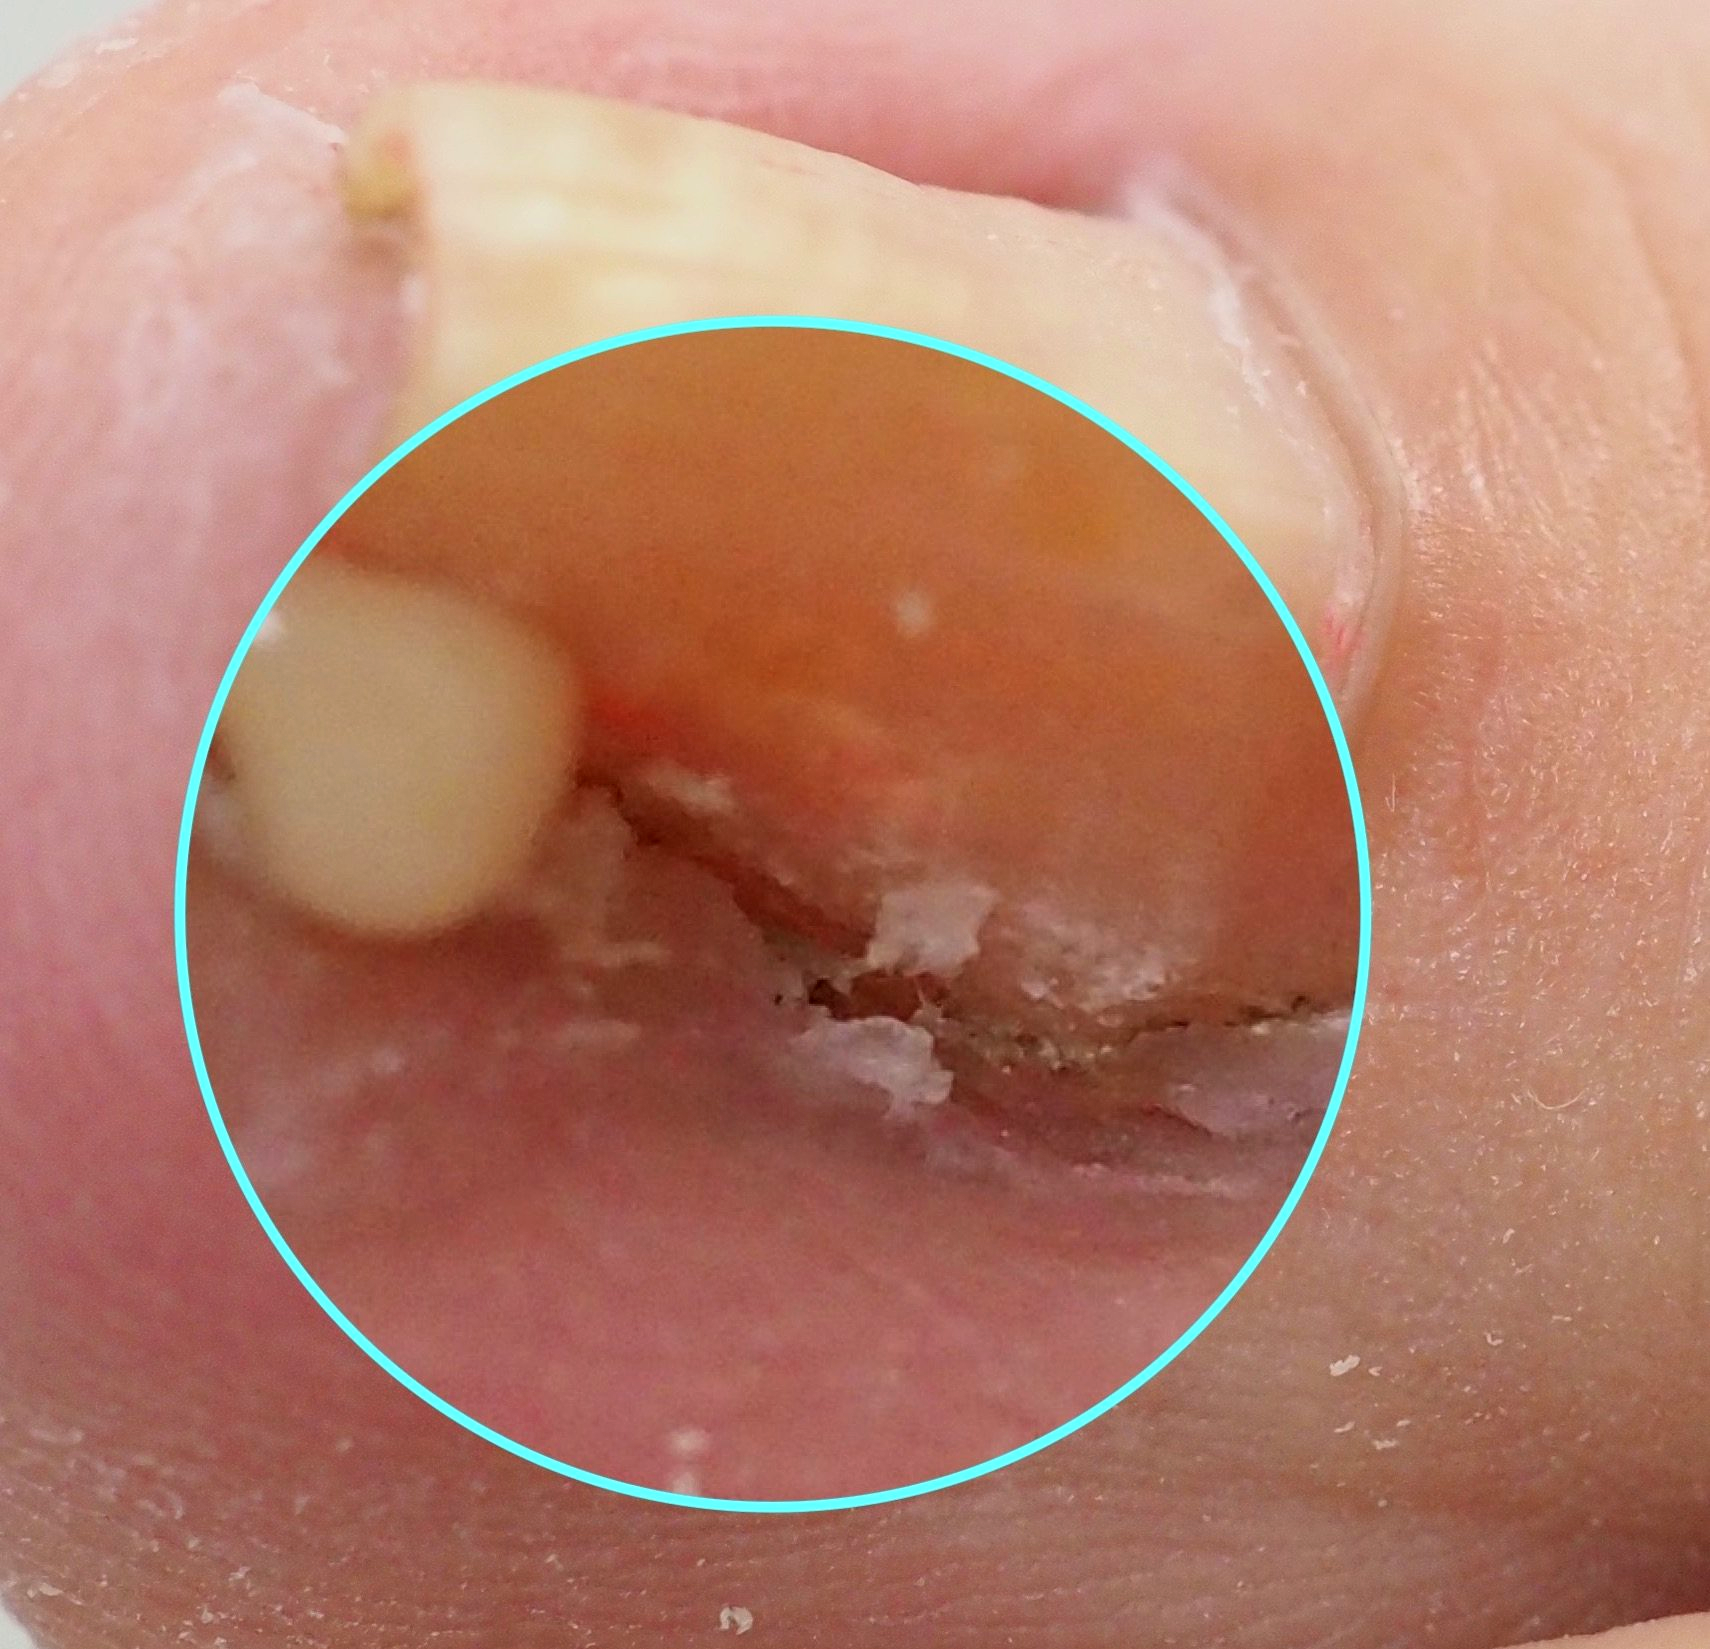

1.) Akutfall am Nagel

👉 Im Folgenden ein Akutfall der besonderen Art:

Kommt nicht sehr oft aber doch immer wieder einmal vor.

🔴 Der Nagelspan kommt bereits DURCH das Weichgewebe.

In Vergrößerung am Monitor auf Bild 2